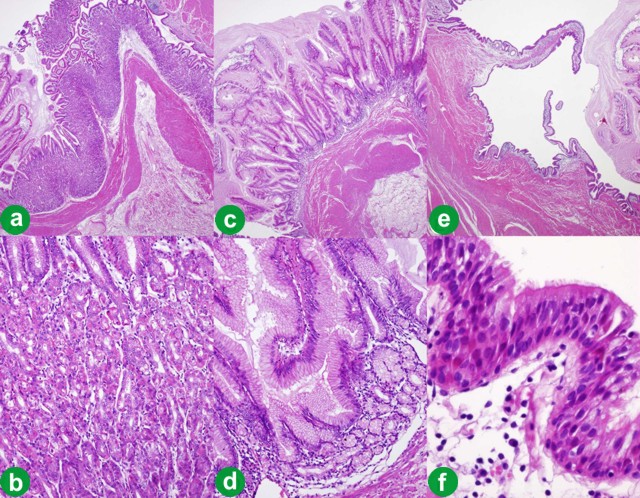

A 38-year-old woman with a previous diagnosis of ileal Crohn’s disease, presented to our institution complaining of epigastric discomfort, bloating, postprandial nausea and 2-3 bowel movements per day. She had no history of pancreatitis and an unremarkable gynecologic history. The patient was further investigated with abdominal ultrasonography and computerized scan tomography (CT) which revealed a large cystic mass (8.5 cm diameter) in the pancreatic tail (displacing the stomach wall) (Figure 1a). Fine needle-aspiration showed a mucinous content with detritus and acellular fluid. The patient underwent a distal pancreatectomy with splenectomy. No communication between the pancreatic mass and the lumen of the stomach was assessed. The postoperative course was uneventful. The patient remains free of symptoms 10 years after the procedure. Pathological study revealed a 9.5 cm diameter cystic mass with a homogeneous wall (Figure 1b). Part of the cyst was lined with gastric mucosa surrounded by a wall of muscularis propria well delineated from the normal pancreas tissue (Figure 2ab). A focal hyperplasia of simple cuboid epithelium and ciliated pseudostratified epithelium was observed (Figure 2cdef). The diagnosis of a gastric duplication cyst (foregut choristoma) of the pancreas was made.

Figure 2. Microscopic aspect of the cyst wall. Some areas are lined by gastric-type mucosa, either oxyntic-type (a.; b.: detail of a.), or antral mucosecretory-type epithelium with mild hyperplasia (c.; d.: detail of c.). Flat ciliated pseudostratified epithelium covering other areas of the inner face of the cyst (e.; f.: detail of e.). (H&E; a., c., e.: 15x; b., d.: 200x; f.: 400x). |